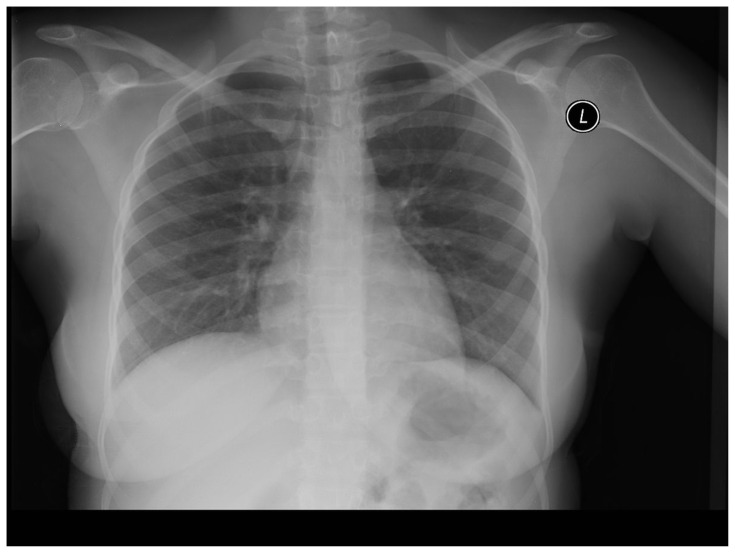

Abstract Image